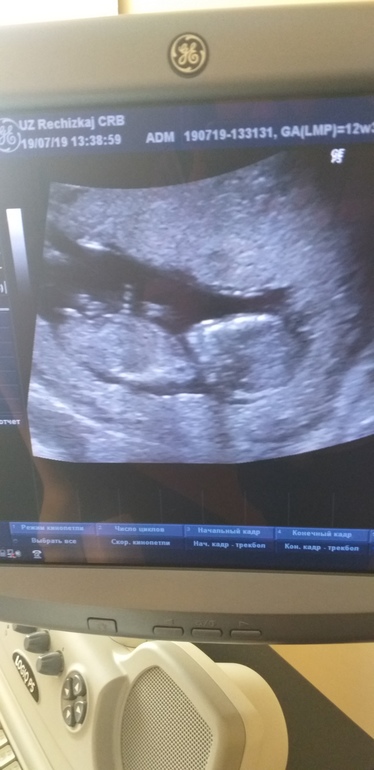

девочки,подскажите может кто у нас будет)врач ничего не говорила)срок 12.5

20.07.2019